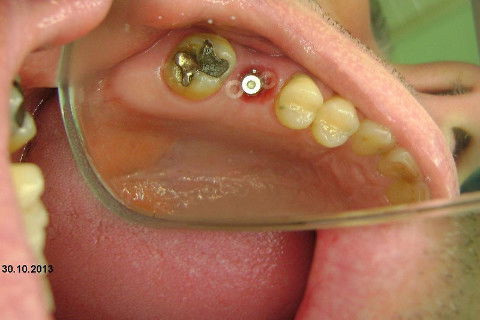

Instalação de um implante em região do 26. Utilizamos um implante cone morse Alvim Neodent 4.3 X 11,5. Foi uma cirurgia muito rápída e minimamente traumática, sem retalho e sutura.